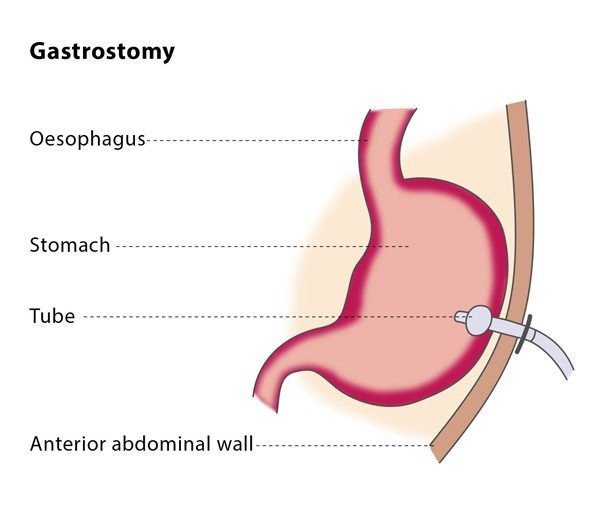

فغر المعدة (فتح المعدة) 2022

فغر المعدة بالمنظار عن طريق الجلد (PEG) هي عملية جراحية لوضع أنبوب تغذية. يسمح لك أنابيب التغذية ، أو أنابيب PEG ، بتلقي التغذية من خلال معدتك. قد تحتاج إلى أنبوب PEG إذا كنت تواجه صعوبة في البلع أو لا يمكنك الحصول على كل التغذية التي تحتاجها عن طريق الفم.

يُعد فغر المعدة من الإجراءات الطبية البسيطة التي يقوم بها طبيب الجهاز الهضمي، وتتم جراحة فغر المعدة بأحد الطرق الآتية:

فغر المعدة بالمنظار عن طريق الجلد (PEG)

هذا النوع من فغر المعدة يعد الأكثر انتشارًا كونه أقل توغلا من الطريقة الأخرى وأقل تأثيرًا على المُصاب من الناحية البدنية والنفسية.

يستخدم طبيبك أنبوبًا مرنًا مضاءً يسمى المنظار لتوجيه عملية إنشاء فتحة صغيرة عبر جلد الجزء العلوي من البطن وصولاً إلى المعدة مباشرةً. يسمح هذا الإجراء للطبيب بوضع وتأمين أنبوب تغذية في المعدة. يتلقى المرضى عمومًا مخدرًا وريديًا ومخدرًا موضعيًا ، ويتم إعطاء مضاد حيوي عن طريق الوريد قبل الإجراء. يمكن للمرضى عادة العودة إلى المنزل في يوم الإجراء أو في اليوم التالي.

يتم هذا الإجراء بمدة زمنية محصورة بين 30 – 45 دقيقة، وغالبًا لا يتطلب الإقامة بالمستشفى، إذ يُمكن للمريض العودة إلى منزله بعد إعطائه النصائح الطبيب للتعامل مع هذا القعر.